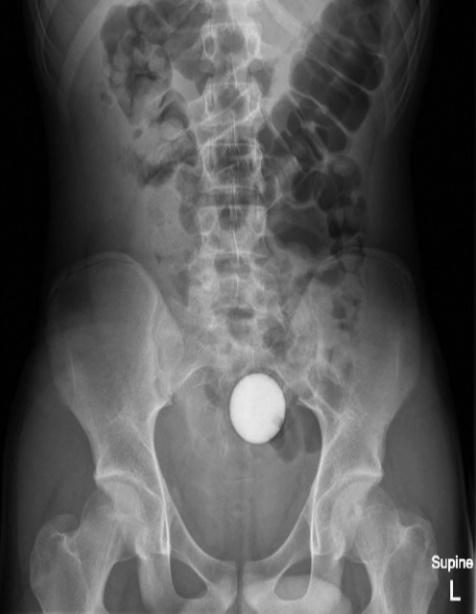

醫生建議治療方法首選是瀉藥

24小時後,醫生再為少年照X光,但高爾夫球依然卡在腹腔,但少年的家屬不願意再讓少年接受入侵性治療,因此醫生轉開大量瀉藥,令少年最終「屙」出這顆高爾夫球,少年的腸道及胃道亦沒有受損,身體狀況一切正常,隨後就讓少年出院,但也警告他「不要再將東西塞入肛門直腸」。醫師除了在期刊上公開這起病例,亦在報告中強調,如果有異物進入病患體內,若病患的腸胃道正常的情況下,建議治療方法首選是瀉藥,以用最自然的方法將異物排出。